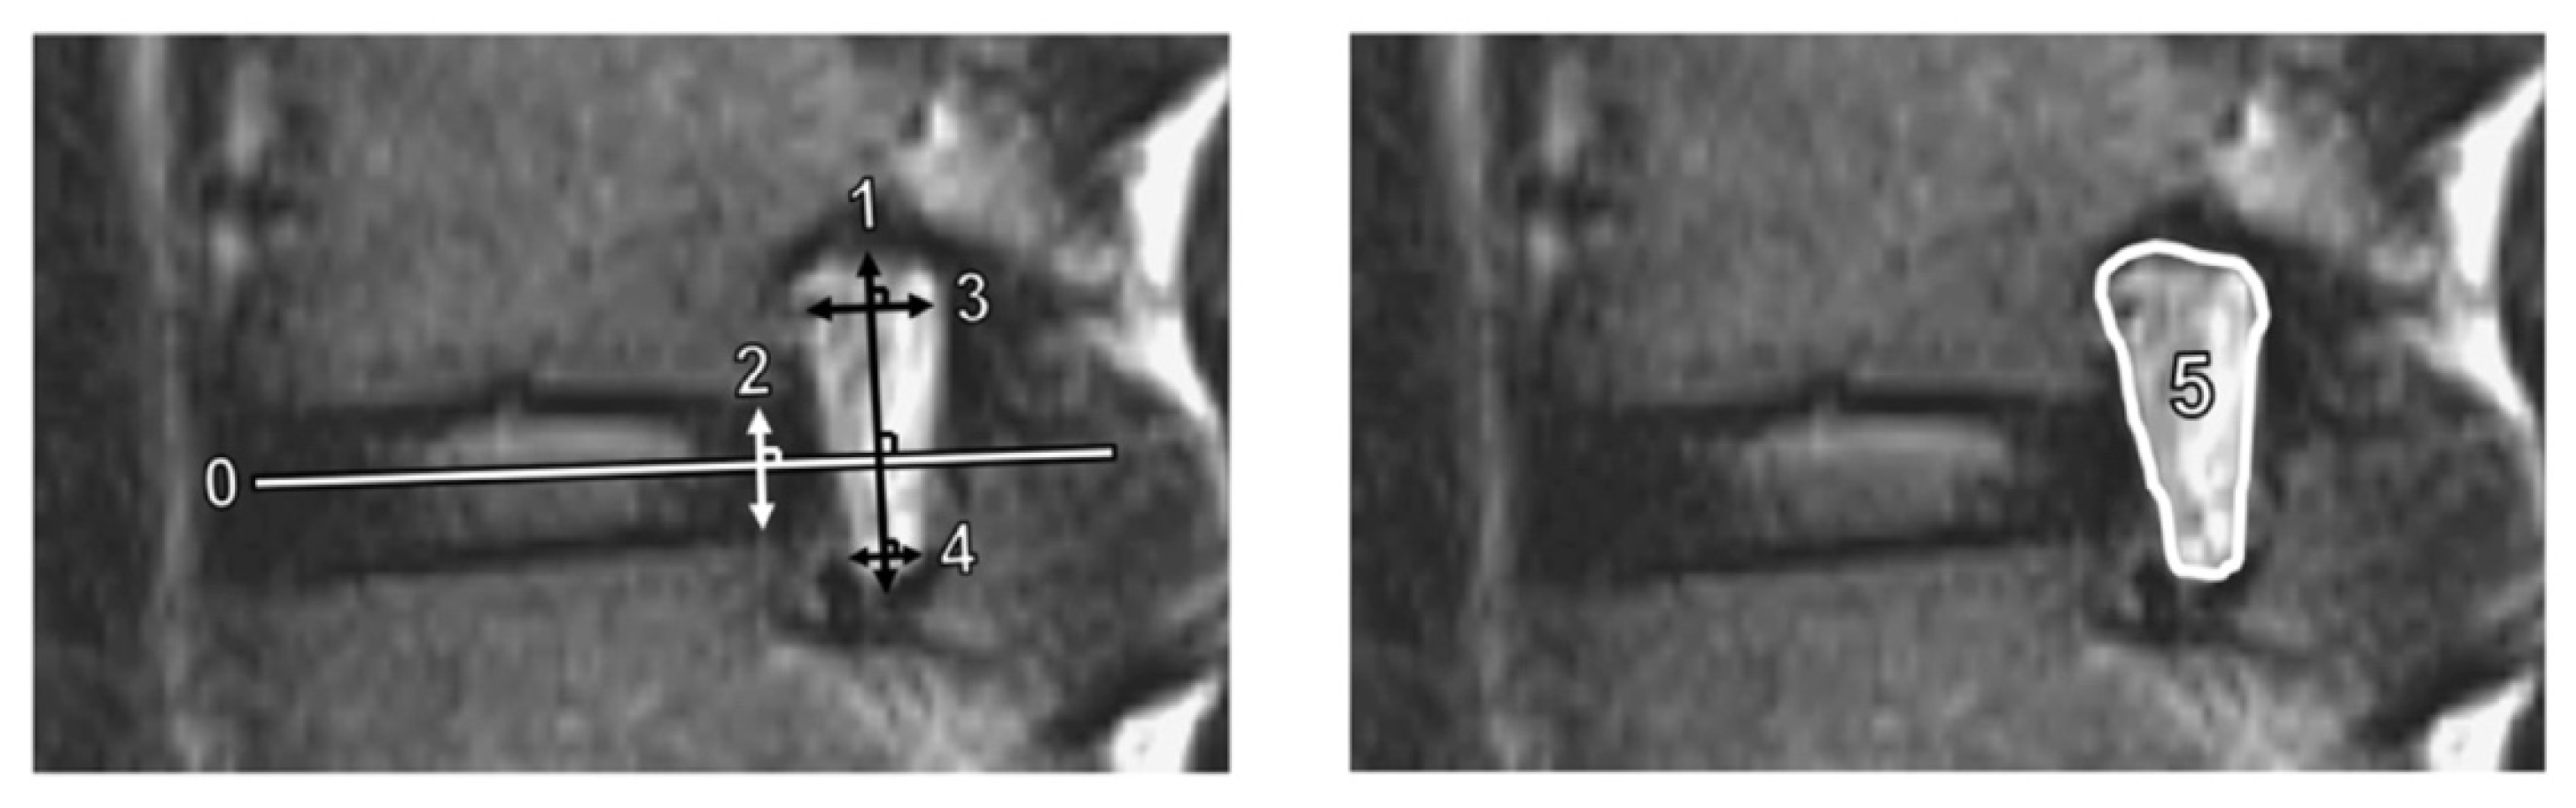

2.2. MRI Parameters and PRO Measurement

| Foraminal height, mm | 16.5 (14.5, 18.3) |

| Disc height, mm | 5.5 (4.3, 6.4) |

| Superior foraminal width, mm | 8.1 (6.4, 9.1) |

| Inferior foraminal width, mm | 2.4 (0.0, 3.2) |

| Foraminal area, mm2 | 63.0 (48.8, 79.3) |